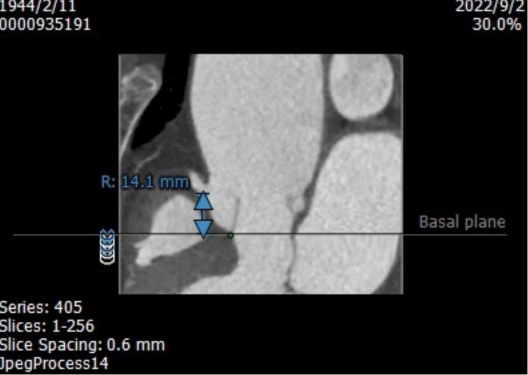

CT评估

收缩期瓣环:70.3mm

收缩期流出道:72.2mm

舒张期瓣环:68.1mm

舒张期流出道:73.1mm

左冠高度10.8mm

右冠高度14.1mm

主动脉窦宽:32.8mm、31.3mm、32.4mm

窦管结合部:113.9mm

升主动脉:146.6mm